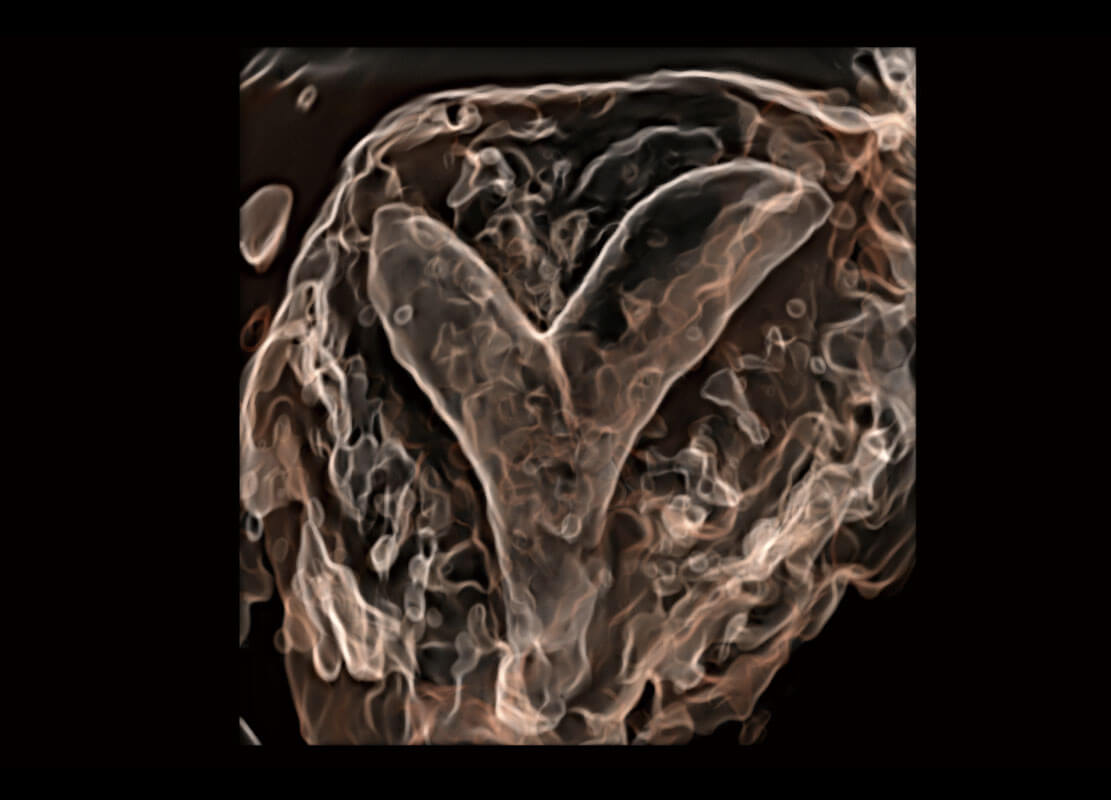

腔内三维-宫内节育器

腔内三维-光影成像

高分辨率容积成像-早孕胎儿

光影成像-孕囊